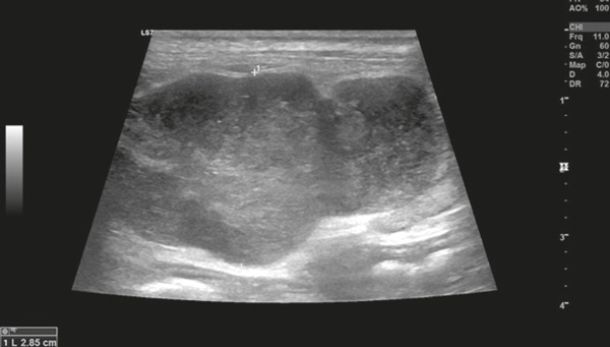

Diagnostic imaging forms a crucial part of clinical workup. Abdominal radiography might not be helpful as the changes in the gastrointestinal tract associated with AL depend on the disease severity, but we can observe a loss of detail or mass effect either due to the gastrointestinal mass and/or lymphadenomegaly or, less often, due to free abdominal fluid. Abdominal ultrasound is more commonly used. The most frequent ultrasonographic abnormality observed is abnormal wall layering with or without concurrent increase in wall thickness (Figure 1). The extent of wall changes can be highly variable in dogs with intestinal lymphoma. Where sonographic abnormalities were present, lesions have been characterised as: predominantly hypoechoic, focal or multifocal ulcerations, small hypoechoic nodules to larger masses (Figure 2) and enlarged abdominal lymph nodes (Figure 3). In some cases abdominal effusion may be present as well. The sonographic appearance of gastrointestinal lymphoma is variable and can overlap with that of a normal bowel, especially in cases of small cell or low-grade AL. Lastly, diffuse intestinal thickening has also been reported and it should be differentiated from enteritis. It is important to note that even when no ultrasonographical abnormalities are found, AL cannot be ruled out without obtaining biopsies of the gastrointestinal tract.